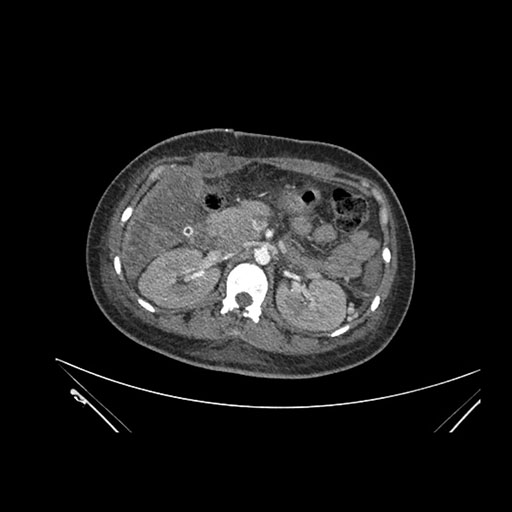

Imaging Analysis

Look through the patient's CT scan to identify any areas of concern for the necessary procedure.

Axial Arterial

Based on initial findings, which issue(s) would you be most concerned about?